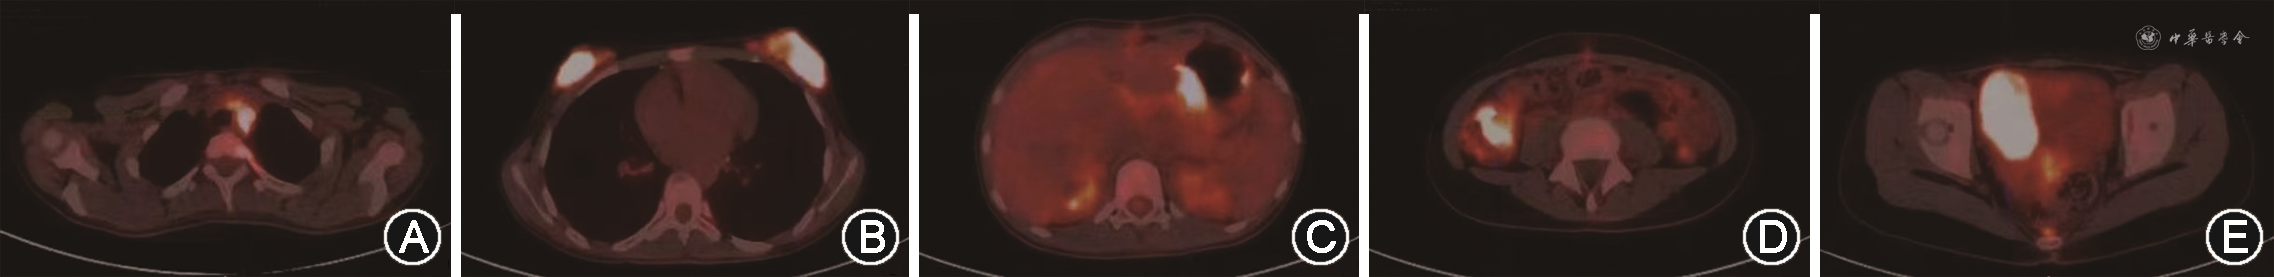

辅助检查(括号内为参考值范围):血常规示白细胞计数11.7×109/L(5.2×109~9.1×109/L),中性粒细胞计数9.9×109/L(1.8×109~6.3×109/L),红细胞计数3.0×1012/L(4.0×1012~4.5×1012/L),血红蛋白85 g/L(115~150 g/L),血小板计数260×109/L(125×109~350×109/L)。生化检查示丙氨酸转氨酶409 U/L(9~52 U/L),天冬氨酸转氨酶488 U/L(14~36 U/L),γ谷氨酰转移酶262 U/L(38~126 U/L),白蛋白28 g/L(35~50 g/L),总胆红素73 μmol/L(0~20 μmol/L),结合胆红素52.6 μmol/L(0~6.8 μmol/L),未结合胆红素20 μmol/L(0~19 μmol/L),乳酸脱氢酶991 U/L(313~618 U/L),脂肪酶 1 951 U/L(23~300 U/L),血淀粉酶582 U/L(30~110 U/L),尿淀粉酶 1 542 U/L(0~450 U/L)。肿瘤六项正常。胰十二指肠术后病理蜡块至上海市临床病理读片会会诊示(小肠)髓系肉瘤侵及胰腺,免疫组织化学示肿瘤细胞CD20-,CD79a-,TDT-,CD99-,CD3-,CD10-,CD43+,CD34+,Ki67+(约60%),CKpan-,BCL2+,cyclinD1-,MPO+,CD68-,Lysozyme-。盆腔B超提示实质性占位(61 mm×41 mm×34 mm),盆腔增强磁共振成像示盆腔右侧占位,考虑来源右侧卵巢,性索间质肿瘤或转移瘤可能。18F-氟脱氧葡萄糖(18F-fluorodeoxyglucose,18F-FDG)正电子发射计算机断层显像(positron emission tomography-computed tomography,PET-CT)示胃、右半结肠、右侧附件区、双侧乳腺、左上胸腔胸膜、前中上纵隔及左侧腋窝淋巴结、左侧筛窦多发病变,伴18F-FDG代谢增高,考虑髓系源性恶性肿瘤(图1)。盆腔占位组织穿刺病理提示为髓系肉瘤。血涂片及骨髓涂片、活检、免疫分型均未见异常;融合基因检测:TLS-ERG融合基因阳性;染色体核型G带、R带分析:46,XX,t(16;21)(p11;q22)[2]。

根据患儿临床表现、占位组织病理、PET-CT及骨髓融合基因、染色体等检查,诊断为伴t(16;21)(p11;q22)及TLS-ERG融合基因多发性原发性髓系肉瘤。予IHA方案(伊达比星+高三尖杉酯碱+阿糖胞苷)化疗1个疗程,后患儿至外院予DAE方案(柔红霉素+阿糖胞苷+依托泊苷)、DAC+HAG方案(地西他滨+高三尖杉酯碱+阿糖胞苷+粒细胞集落刺激因子)及CLAG方案(克拉屈滨+阿糖胞苷+粒细胞集落刺激因子)化疗3个疗程。复查PET-CT未完全缓解,2021年7月行亲缘半相合异基因造血干细胞移植(allogeneic hematopoietic stem cell transplantation,allo-HSCT)(父供女)治疗,移植成功后予阿扎胞苷单药维持治疗6个疗程,复查骨髓细胞学、免疫分型、融合基因、染色体均未见异常,PET-CT提示影像学完全缓解,病情平稳,仍随访中。

髓系肉瘤是一种较为少见的由髓系不成熟细胞浸润至髓外组织形成的肿瘤,常见发病部位为淋巴结、皮肤和软组织、骨骼、睾丸、胃肠道和腹膜等[1]。髓系肉瘤常为儿童急性髓系白血病(acute myeloid leukemia,AML)的一种特殊临床表现或髓外复发表现,发生率可高达40%,孤立性(原发性)髓系肉瘤即无髓系肿瘤病史或无血液、骨髓浸润,临床罕见,累及多部位者则更为罕见。原发于十二指肠或胰腺、胆囊部位的髓系肉瘤发病率极低[1],早期极易被误诊为其他实体恶性肿瘤,甚至实施不必要的根治手术。本例患儿为11岁女童,初发表现为梗阻性黄疸,早期仅发现胰十二指肠占位,因未考虑到淋巴造血系统肿瘤可能,进行“根治性胰十二指肠切除术”后病理最终确诊为髓系肉瘤。手术后患儿病情仍迅速进展,完善PET-CT检查后发现患儿不仅有胃、淋巴结、骨骼等常见部位侵犯,还有结肠、胰腺、胸膜、乳腺、附件区等少见部位侵犯,体现出PET-CT对髓系肉瘤影像学诊断的价值,此类患儿如能早期行PET-CT检查提示多发性髓系肉瘤,可避免大的创伤性手术,并为后期尽早化疗、allo-HSCT等治疗后的疗效评估提供全面支持,提高生活质量。